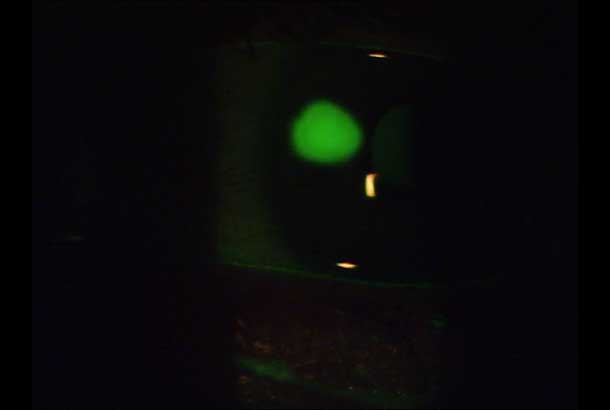

"name": "H. Sclerotic Scatter",

"detail": "<h2>&nbsp;</h2>\n\n<h2>Overview</h2>\n\n<ul>\n\t<li>The technique uses&nbsp;total internal reflection of the cornea</li>\n\t<li>It allows the cornea to be assessed for the presence of edema or corneal opacities</li>\n\t<li>The illumination and observation systems are uncoupled</li>\n</ul>\n\n<p>&nbsp;</p>\n\n<h2>Set Up</h2>\n\n<ul>\n\t<li>The illumination system is uncoupled from the observation system</li>\n\t<li>Low magnification is used</li>\n\t<li>A moderate width light beam is directed at the limbus</li>\n\t<li>The observation system is focussed on the central cornea</li>\n\t<li>When total internal reflection is acheived, the whole limbus is illuminated</li>\n</ul>\n\n<p>&nbsp;</p>\n\n<h2>Useful when assessing</h2>\n\n<ul>\n\t<li><a href=\"/condition/14\">Corneal Edema - Stromal</a></li>\n\t<li><a href=\"/condition/27\">Corneal Opacities</a></li>\n</ul>\n\n<p>&nbsp;</p>\n\n<p>&nbsp;</p>",